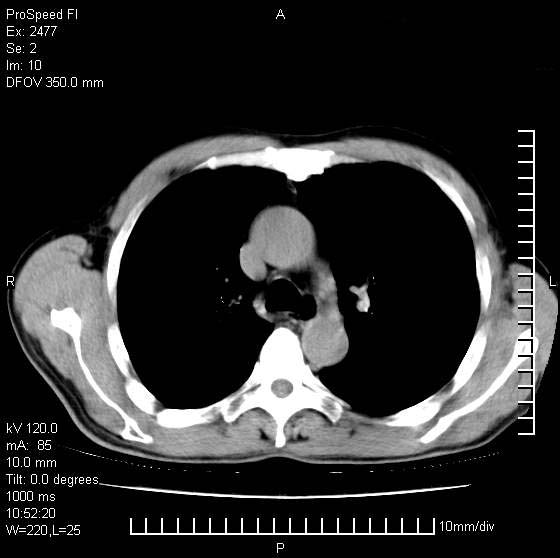

以下是引用天南地北在2007-10-9 14:29:00的发言:[br]1:右上肺结核[br]2:右肺下叶肿块:不支持肺癌,首先考虑炎性病变-肺脓疡可能性大[br]理由:1:临床病史支持,肺脓肿症状不明显应该是不规则服药造成。[br] 2:肿块边缘模糊,周围可见炎性渗出,长毛刺,内见支气管征,不过有点不规则。[br] 我感觉下肺癌这个诊断有点偏左,建议积极抗炎治疗后复查

以下是引用卜一在2007-10-9 15:55:00的发言:[br][br] [br] 1:右上肺结核[br]2:右肺下叶肿块:不支持肺癌,首先考虑炎性病变-肺脓疡可能性大[br]理由:1:临床病史支持,肺脓肿症状不明显应该是不规则服药造成。[br] 2:肿块边缘模糊,周围可见炎性渗出,长毛刺,内见空气支气管征,不过有点不规则。[br] 我感觉下肺癌这个诊断有点偏左,建议积极抗炎治疗后复查![br]支持! [br] [br] [br]

以下是引用hhcckk在2007-10-9 15:18:00的发言:[br]右上肺病灶考虑结核,病灶多种形态并存(纤维化、增殖性病灶并存)[br]右下肺病灶比较难说,个人意见更趋向于“天南地北”的诊断----肺脓肿[br]1、病人有明显的寒战,高热,肿瘤病人很少出现[br]2、病灶周围的肺纹理走向柔和,没有肿瘤病灶常见的集束征[br]3、病灶边缘的毛刺较长,恶性肿瘤多为短毛刺[br]痰中血丝和病人的年龄是两个不利于良性肿块的因素,建议早点活检

以下是引用ydx_74在2007-10-9 15:53:00的发言:[br]右上肺结核,右下中心性肺癌可能大,肺门淋巴结肿大。